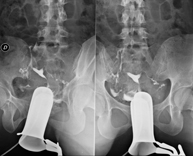

La cistouretrografía miccional seriada consiste en la obtención de imágenes radiológicas para valorar la anatomía y la función de la uretra y la vejiga con la administración de contraste yodado a través de una sonda vesical. - Uretrocistografía (Uretro-Cums)

La uretrocistrografía retrógrada y miccional consiste en la obtención de imágenes radiológicas para valorar la anatomía y la función de la vejiga y de la uretra. Se aplica material de contraste a través de una pequeña sonda alojada en la uretra y se obtienen imágenes durante el llenado y vaciado de la vejiga. - Pielografía ascendente por catéter

La cistouretrografía miccional seriada consiste en la obtención de imágenes radiológicas para valorar la anatomía y la función de la uretra y la vejiga con la administración de contraste yodado a través de una sonda vesical.